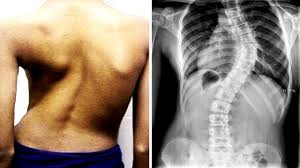

Deformidades

Alteraciones en la alineación de la columna, como escoliosis o cifosis, que pueden causar dolor y afectar la postura y función.